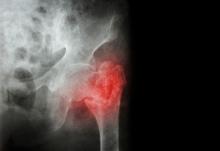

Peripheral Nerve Blocks for Hip Fractures

JAMA reviews the use of peripheral nerve block with hip fractures as an effective pain management strategy that can be performed by credentialed clinicians outside of the operating room.

Hip fractures are common, especially in older adults (≥65 years), and may include a 1-year mortality rate of 12% to 25%. In the US, there were approximately 290 130 hospitalizations and 7731 deaths related to hip fractures in 2019.